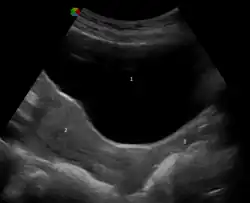

Ultraschallbild von 1: Harnblase; 2: Gebärmutter; 3: Vagina -